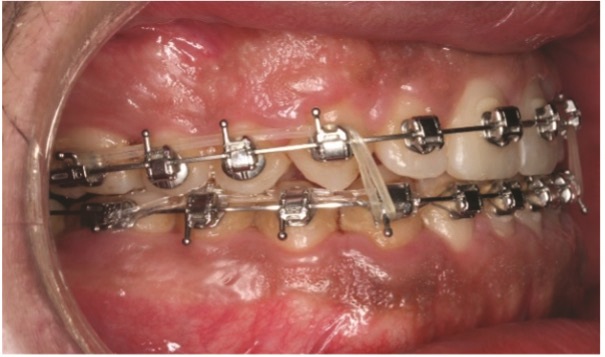

On the fourth visit, six months into treatment, 0.014-by-0.025- inch thermally activated nickel titanium wires (Thermal Ultra) were inserted in both arches, and full lower-arch distalization was carried out using the buccal shelf TADs.

On the seventh visit, eight months into treatment, 0.018-by-0.025- inch thermally activated nickel titanium wires (Thermal Ultra) were engaged on both arches. The force used to connect the TADs to the lower arch was increased progressively from 100 g per side on round nickel titanium wires to 200 g per side when in rectangular nickel titanium wires (Figs. 5a–5c).

dentoskeletal-malocclusion

Fig. 5a

Fig. 5b

Fig. 5c

On the eighth visit, 10 months into treatment, a 0.019-by-0.025- inch stainless steel arch form (Europa II Genius) was engaged in the upper arch, with a figure-eight ligature from 3–3, a tieback from 6 to 3 bilaterally, torque expression on anterior teeth, and flipped anterior brackets to resist the flaring effect of the heavy Class III elastics. On the lower arch, a 0.017-by-0.025-inch stainless steel arch form (Europa II Genius) was engaged, with interproximal reduction from mandibular canine to canine to harmonize the contact points and increase the overjet, to allow the negative torque on upper anterior teeth to upright the incisors into a more aesthetic position (Figs. 6a–6c). The patient was instructed to wear Class III elastics (4-ounce, 5/16-inch) at night for the next couple of months to preserve the bite correction, running from upper 6 to upper 3 down to lower 3 (Figs. 7a and 7b).